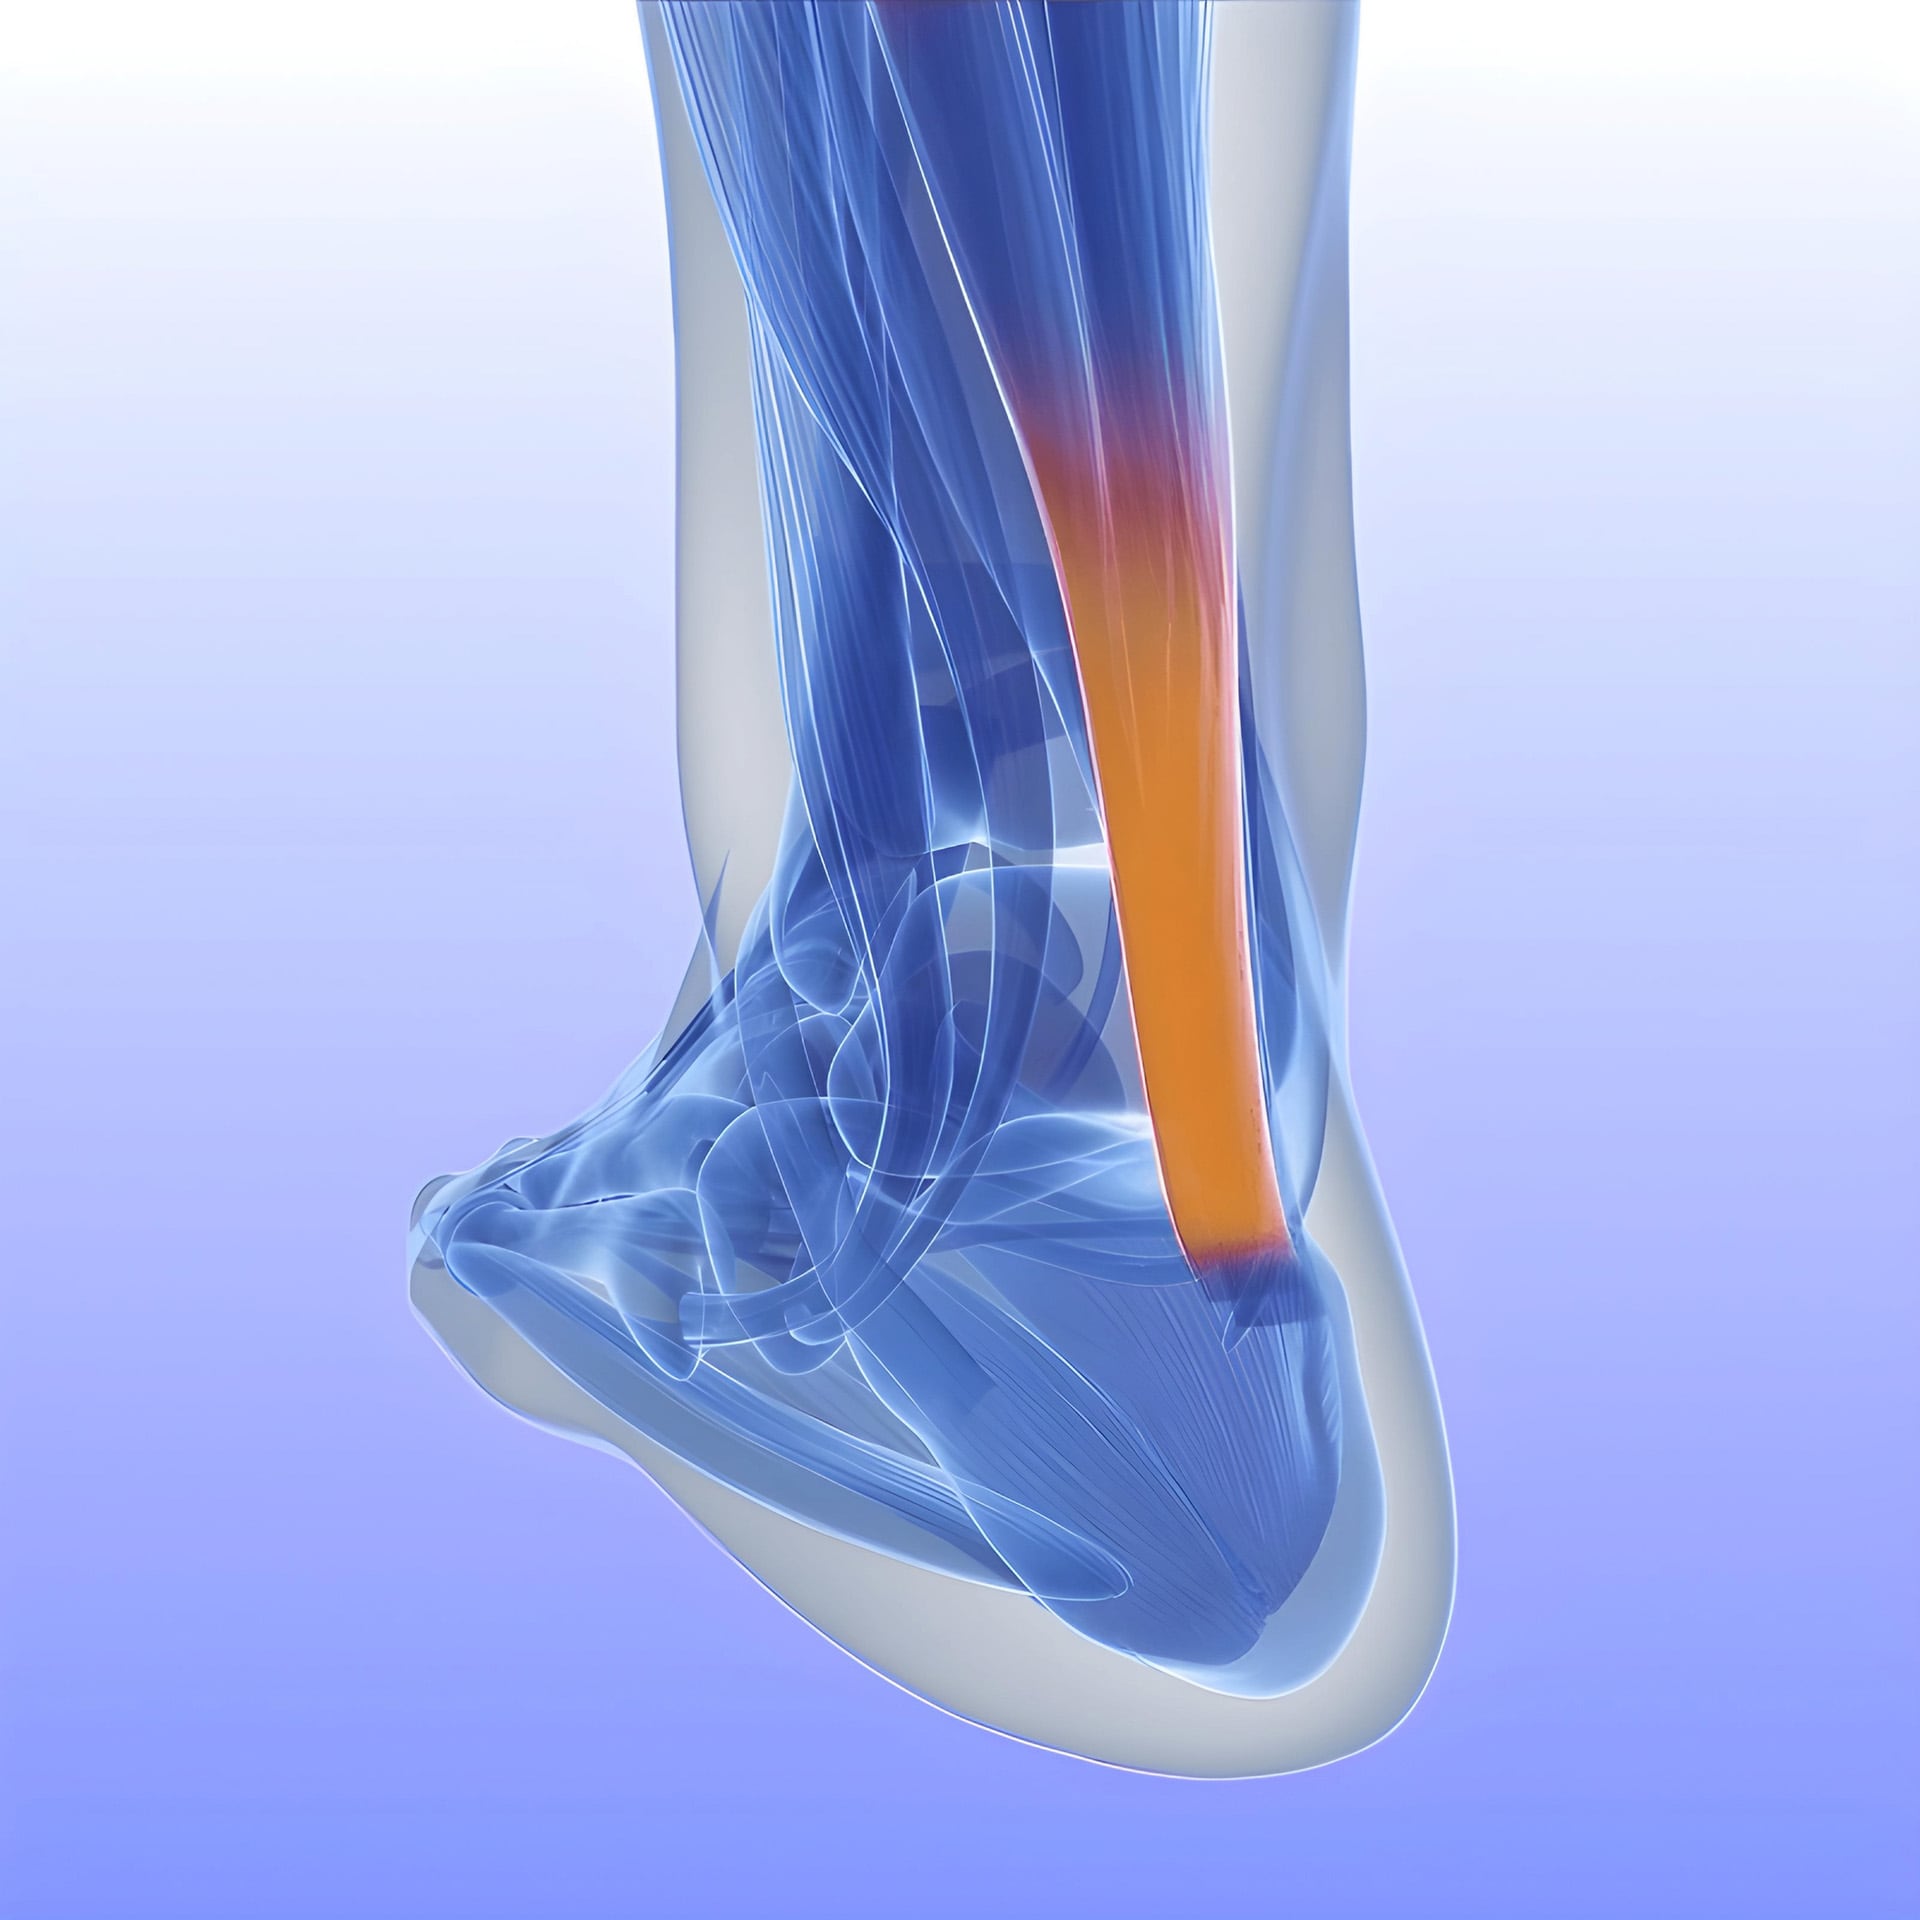

El Instituto de Terapia Regenerativa Tisular (ITRT) del Centro Médico Teknon, centro hospitalario de referencia en España, consiguió regenerar el tendón de Aquiles sin necesidad de cirugía, aplicando células madre mesenquimales autólogas cultivadas.

La técnica se basó en la inyección de células madre derivadas de la médula ósea del propio paciente (aBM-MSC), cultivadas en sala blanca siguiendo estándares de correcta fabricación. El estudio, publicado en la revista médica internacional Journal of Orthopaedics and Sports Medicine, confirmó la recuperación estructural completa del tendón, incluida la eliminación del dolor y el retorno rápido a la actividad deportiva.

El procedimiento consiste en la extracción de células madre mesenquimales de la médula ósea del paciente, su cultivo en condiciones controladas y la posterior inyección en la zona lesionada. Según el equipo del ITRT, la regeneración del tendón ocurre de forma natural y permite la recuperación funcional y estructural sin recurrir a cirugía invasiva.